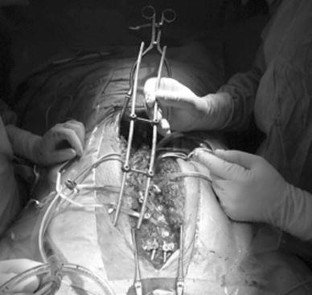

Adolescent idiopathic scoliosis treated with posteromedial translation: radiologic evaluation with a 3D low-dose system

Forty-nine consecutive patients operated for AIS (Lenke 1–4) using posteromedial translation were included. Corrections were evaluated preoperatively, postoperatively and after at least 2 years using the EOS imaging system. 3D angles were measured in the plane of maximum deformity.

Mean number of levels fused and operative time were 13.5 ± 1 and 215 ± 25 min, respectively. Main thoracic, proximal thoracic, and lumbar curves corrections averaged 64.4 ± 18, 31 ± 10 and 69 ± 20 %, respectively. Mean T4–T12 kyphosis increased 18.8° ± 9° in the subgroup of hypokyphotic patients. Mean apical vertebral rotation reduction was 48.3 ± 20 %. Trunk height gain averaged 27.8 ± 14 mm. There was no pseudarthrosis or significant loss of correction in any plane during follow-up. Two patients (4 %) developed asymptomatic proximal junctional kyphosis, despite having normal thoracic kyphosis. Their sagittal balance was shifted posteriorly by 36 and 47 mm, respectively, by the operation, but revision surgery was not performed.

Fig. 4